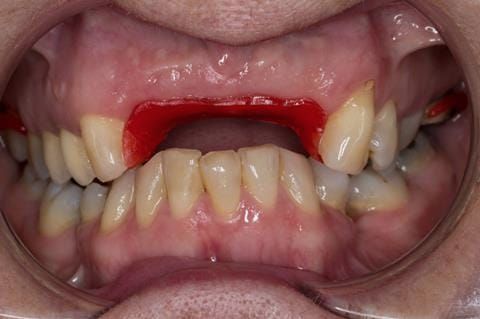

- Extract the upper 2-2 teeth and replace with an interim acrylic based partial denture. Reline the interim denture over 9 - 12 months, replacing with a definitive cobalt chromium based partial denture. The definitive denture would ideally be designed as an occlusal protective splint to reduce the the potential for mechanical wear and breakages of the moderately/heavily restored maxillary dentition. In addition, should further upper teeth require extraction they could be added on to the denture cobalt chromium framework - therefore a new prosthesis would not be required as future teeth are lost. This option would produce an excellent aesthetic outcome. This is the option the patient chose to have.

Following consultation and second discussion appointment the patient chose to have option 3 namely, a maxillary cobalt chromium based partial denture/protective occlusal splint. The clinical situation and treatment process is shown in detail below with photographs. The patient was successfully rehabilitated with this and her quality of life considerably improved. The clinical work was provided by Finlay and the technical work by Rowan.